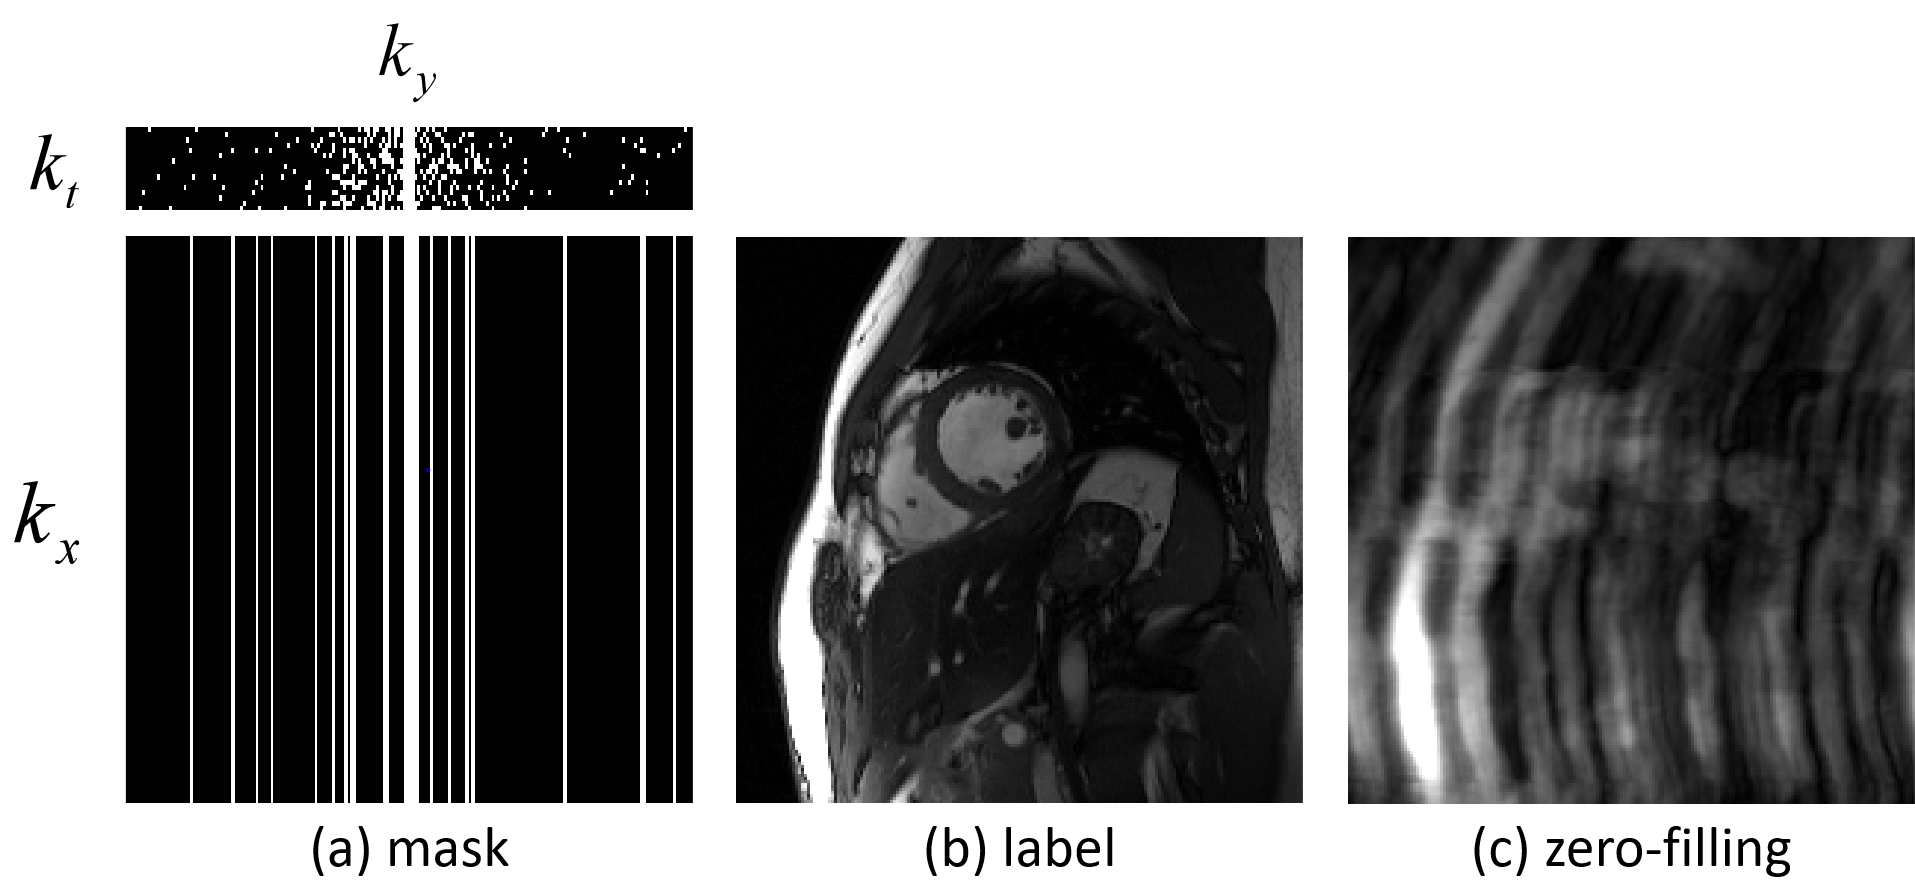

Retrospective undersampling was performed to generate input/output pairs for network training. For each frame, we fully sampled frequency-encodes (along ) and randomly undersampled phase-encodes (along ) according to a zero-mean Gaussian variable density function [5] as shown in Fig.3. Wherein 4 central phase-encodes were ensured to be sampled.